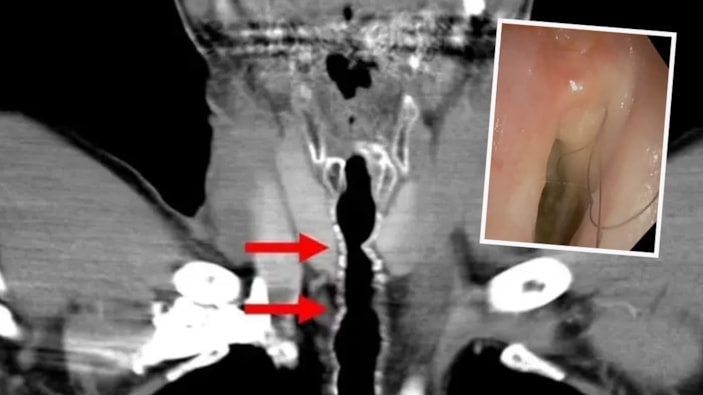

Hastanın şikayeti üzerine yapılan testler sonucunda ortaya çıkan sonuç şaşkına çevirdi. Boğazına gönderilen küçük bir kamera yardımıyla tespit edilen kıllar şaşkınlık yaratırken temizlenmesi de gerçekleştirildi.

Talihsiz hastaya endotrakeal kıllanma veya boğazda kıllanma adı verilen son derece nadir bir durum teşhisi konuldu. Kesin olarak aktarılmasa da doktorlar saç büyümesinin muhtemelen sigara içme alışkanlığından kaynaklandığına inanıyorlar.

American Journal of Case Report'ta yer alan yazılarada, bu tuhaf olayın türünün yalnızca ikinci vakası olduğu aktarıldı. Yine Avusturyalı bilim insanları, sigaranın boğaz iltihabını tetikleyebileceğini ve bunun da hücrelerin kıl köklerine dönüşmesine neden olabileceğini açıkladı.